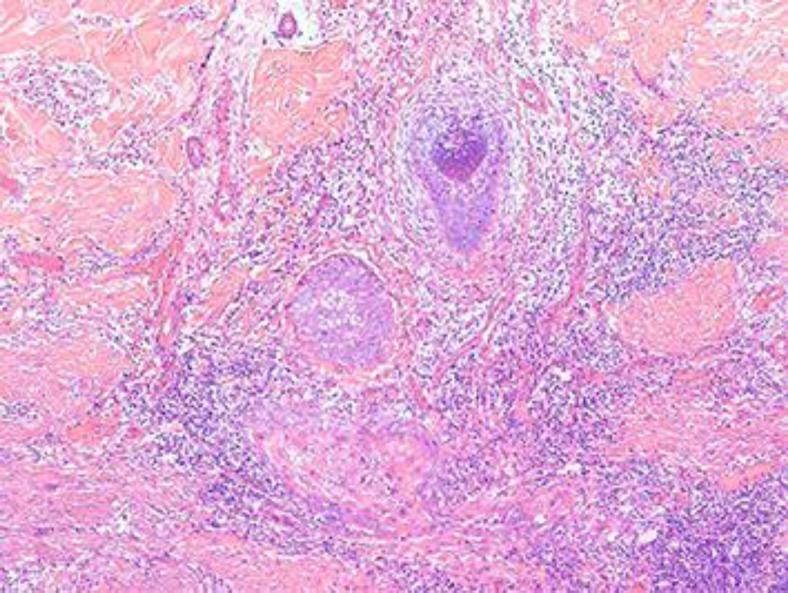

A malignant transformation is known to occur in many nevi such as a sebaceous nevus or a basal cell nevus, but a verrucous epidermal nevus has only rarely been associated with neoplastic changes. Keratoacanthoma, multifocal papillary apocrine adenoma, multiple malignant eccrine poroma, basal cell carcinoma and cutaneous squamous cell carcinoma (CSCC) have all been reported to develop from a verrucous epidermal nevus. CSCC has also been reported to arise from other nevoid lesions like a nevus comedonicus, porokeratosis, a sebaceous nevus, an oral sponge nevus and an ichthyosiform nevus with CHILD syndrome. Here we report a case of progressive poorly differentiated CSCC arising from a localized verrucous epidermal nevus, which caused both spinal cord and brain metastasis.